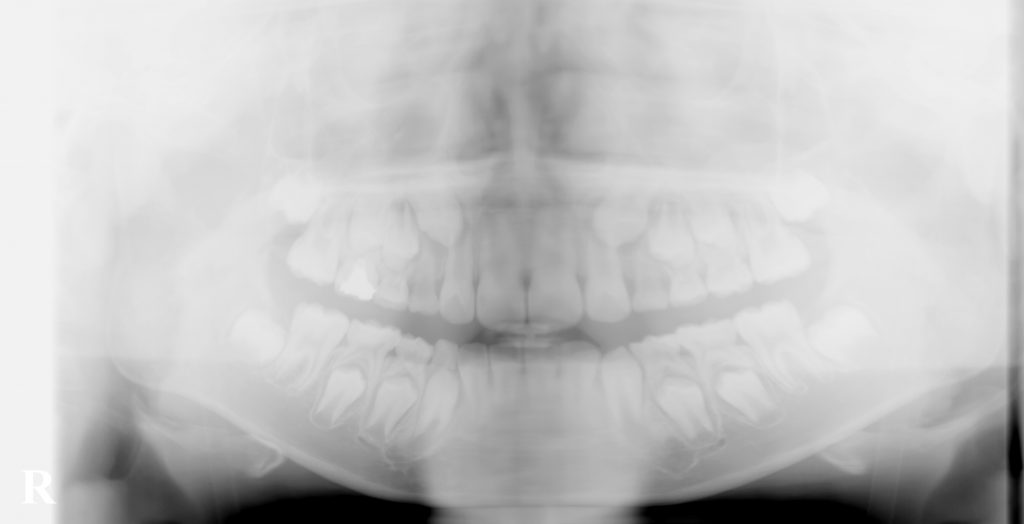

こむら小児歯科・矯正歯科で経過観察してきたケースです。

上の犬歯の位置が悪かったのですが、最終的には問題なく生えてきました。

どんなケースでも矯正治療が必要というわけではなく、正しい診断の元に経過観察することも大切です。

埋まっている上の犬歯を引っ張らなくても このようにきれいに生えてくる事もあります。